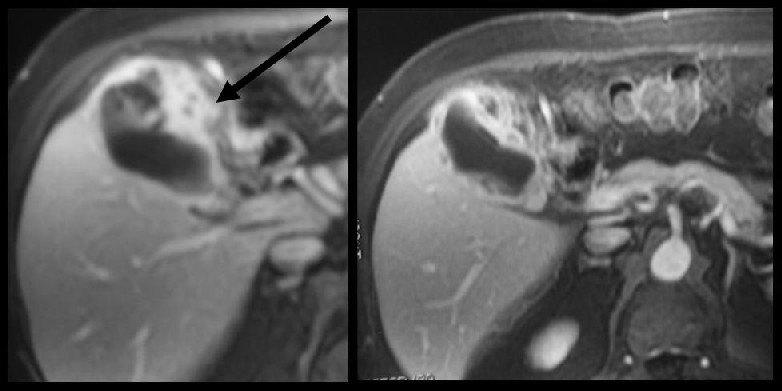

El Colangiocarcinoma son tumores malignos infrecuentes que se originan en la vesícula biliar o en las vías biliares, respectivamente. El tumor de Klatskin es una forma especial de Colangiocarcinoma.

Ciertas patologías de la vesícula biliar y las vías biliares, como la llamada vesícula de porcelana o la enfermedad de Caroli, propician el desarrollo de estos tumores.

Tanto el cáncer de vesícula biliar como el Colangiocarcinoma tienden a invadir de manera temprana órganos cercanos como el duodeno y el páncreas.